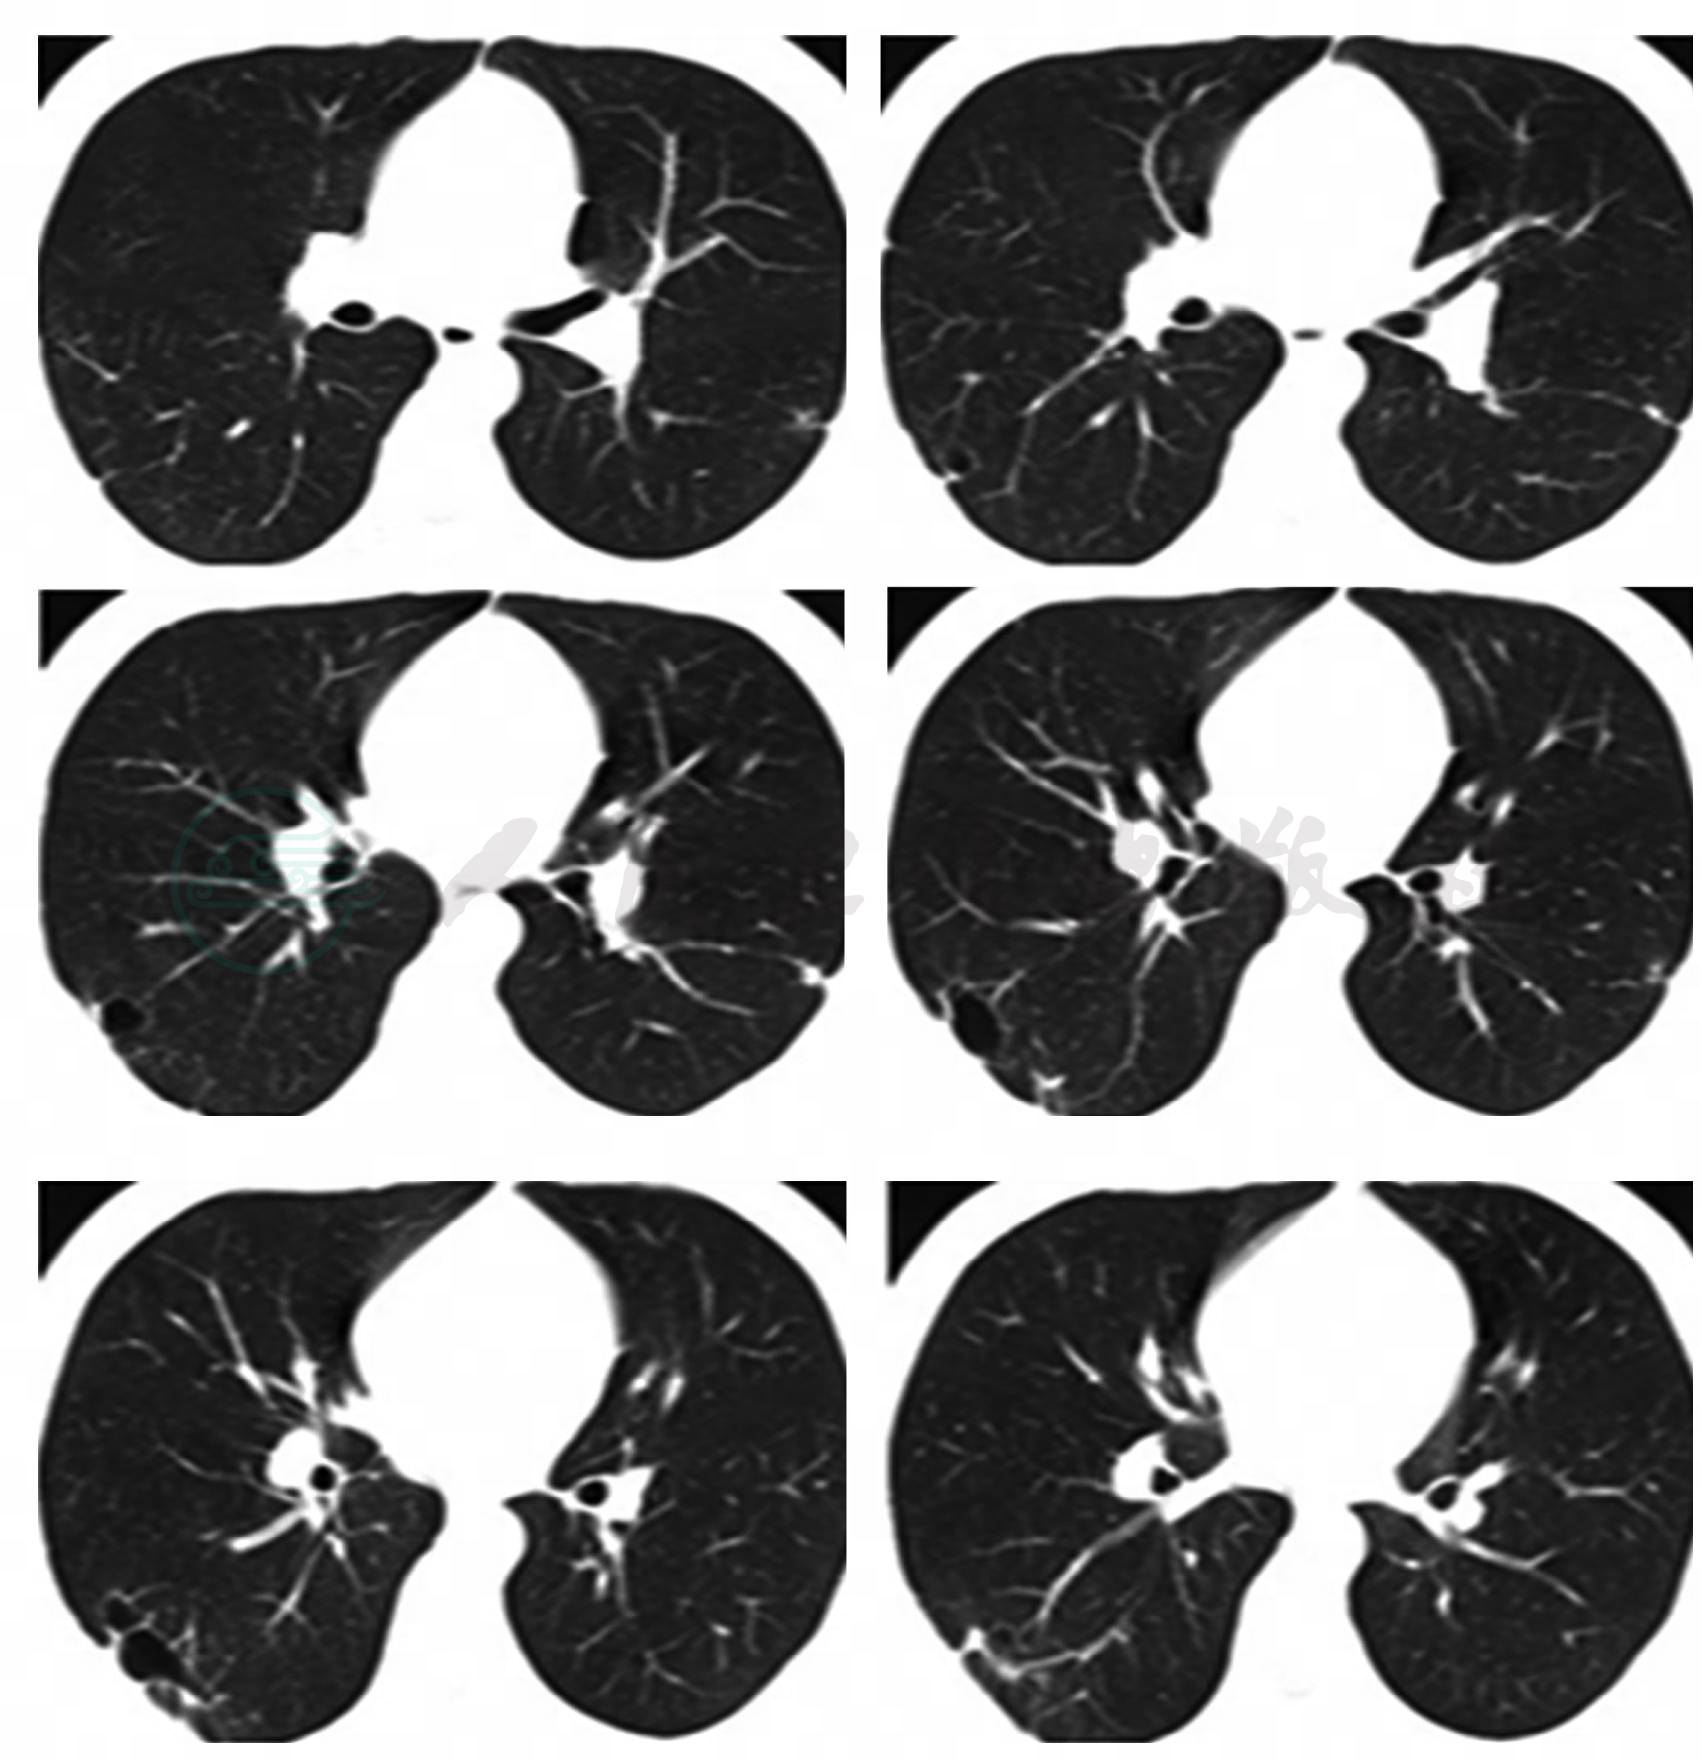

3.胸部CT:右肺下叶外后基底段散在斑片及片状渗出影,部分病灶呈楔形,尖端指向肺门,右下叶后基底段近脊柱旁片状阴影内见密度减低区,病灶与胸膜粘连(图1)。

图1 胸部CT

评价:一个年青体壮、无肺部基础疾病的患者,胸部CT提示右肺下叶散在斑片影就会导致气短?患者无喘息,双肺无干湿啰音,无小气道疾病依据,影像学改变与临床症状之间的“不匹配”没有引起医生的高度重视;对于胸痛伴活动后气短的患者未行血气分析和D-dimer化验等进行常规鉴别诊断分析,导致临床思路偏离了正确方向。